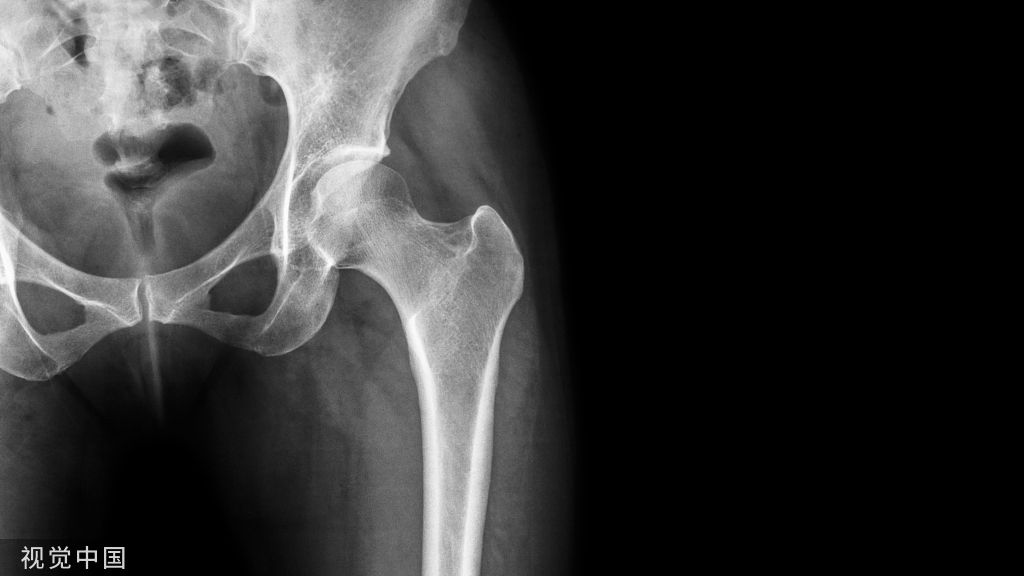

患者取侧卧位。患侧髋关节向上。患侧下肢屈曲20°。内收10°。健侧髋关节屈曲以减少脊柱前凸。手术开始前拍摄前后位x线片,确定骨盆位置。

以股骨大转子为中心做外侧直切口。切口近端略向后方呈弧形。分离阔筋膜张肌。牵开骨外侧肌显露股骨干。在股骨大转子处做常规截骨。将骨块及其所附的外展肌群像近侧牵开,显露前方关节囊。注意保护臀上神经血管束。并从前方切开髋关节囊,将股骨头向前方脱位。避免损伤后方关节囊和外旋肌,以保留股骨头血供。

(二)骨处理

首先处理髋臼。使用半球形扩孔钻处理髋臼,清理髋臼内侧骨质。內移髋臼至骨盆内侧壁。清理股骨头骨赘后,使用大号股骨头凹面铰刀对股骨头塑型。以确保两侧松质骨能够紧密贴合。将髋关节复位后评估骨节处区域。

将下肢放置于屈曲20°、外旋5°,内收15°的位置。正常情况下股骨相对于骨盆5°~10°内收,而外侧接骨板加压固定后内收角度将有所减小,因此接骨板初始放置位置时股骨的位置应该比预期位置多内收10°。选择合适型号的眼镜蛇接骨板根据股骨外形状塑性。使其紧密贴附于股骨外侧。用螺钉把接骨板近端中心固定于骨盆上,并对接骨板远端适当加压。术中透视确定股骨相对于骨盆的内收角度在10°~20°之间。以确保加压完成后股骨位置正确。位置满意后,拧入剩余螺钉,可再次透视确保固定位置良好。拧入近端螺钉前一定要确保髋关节屈曲角度正确。拧入远端螺钉前则需保证股骨旋转角度正确。最后使用皮质骨螺钉将股骨大转子重新固定于解剖位置,恢复外展肌长度和张力。